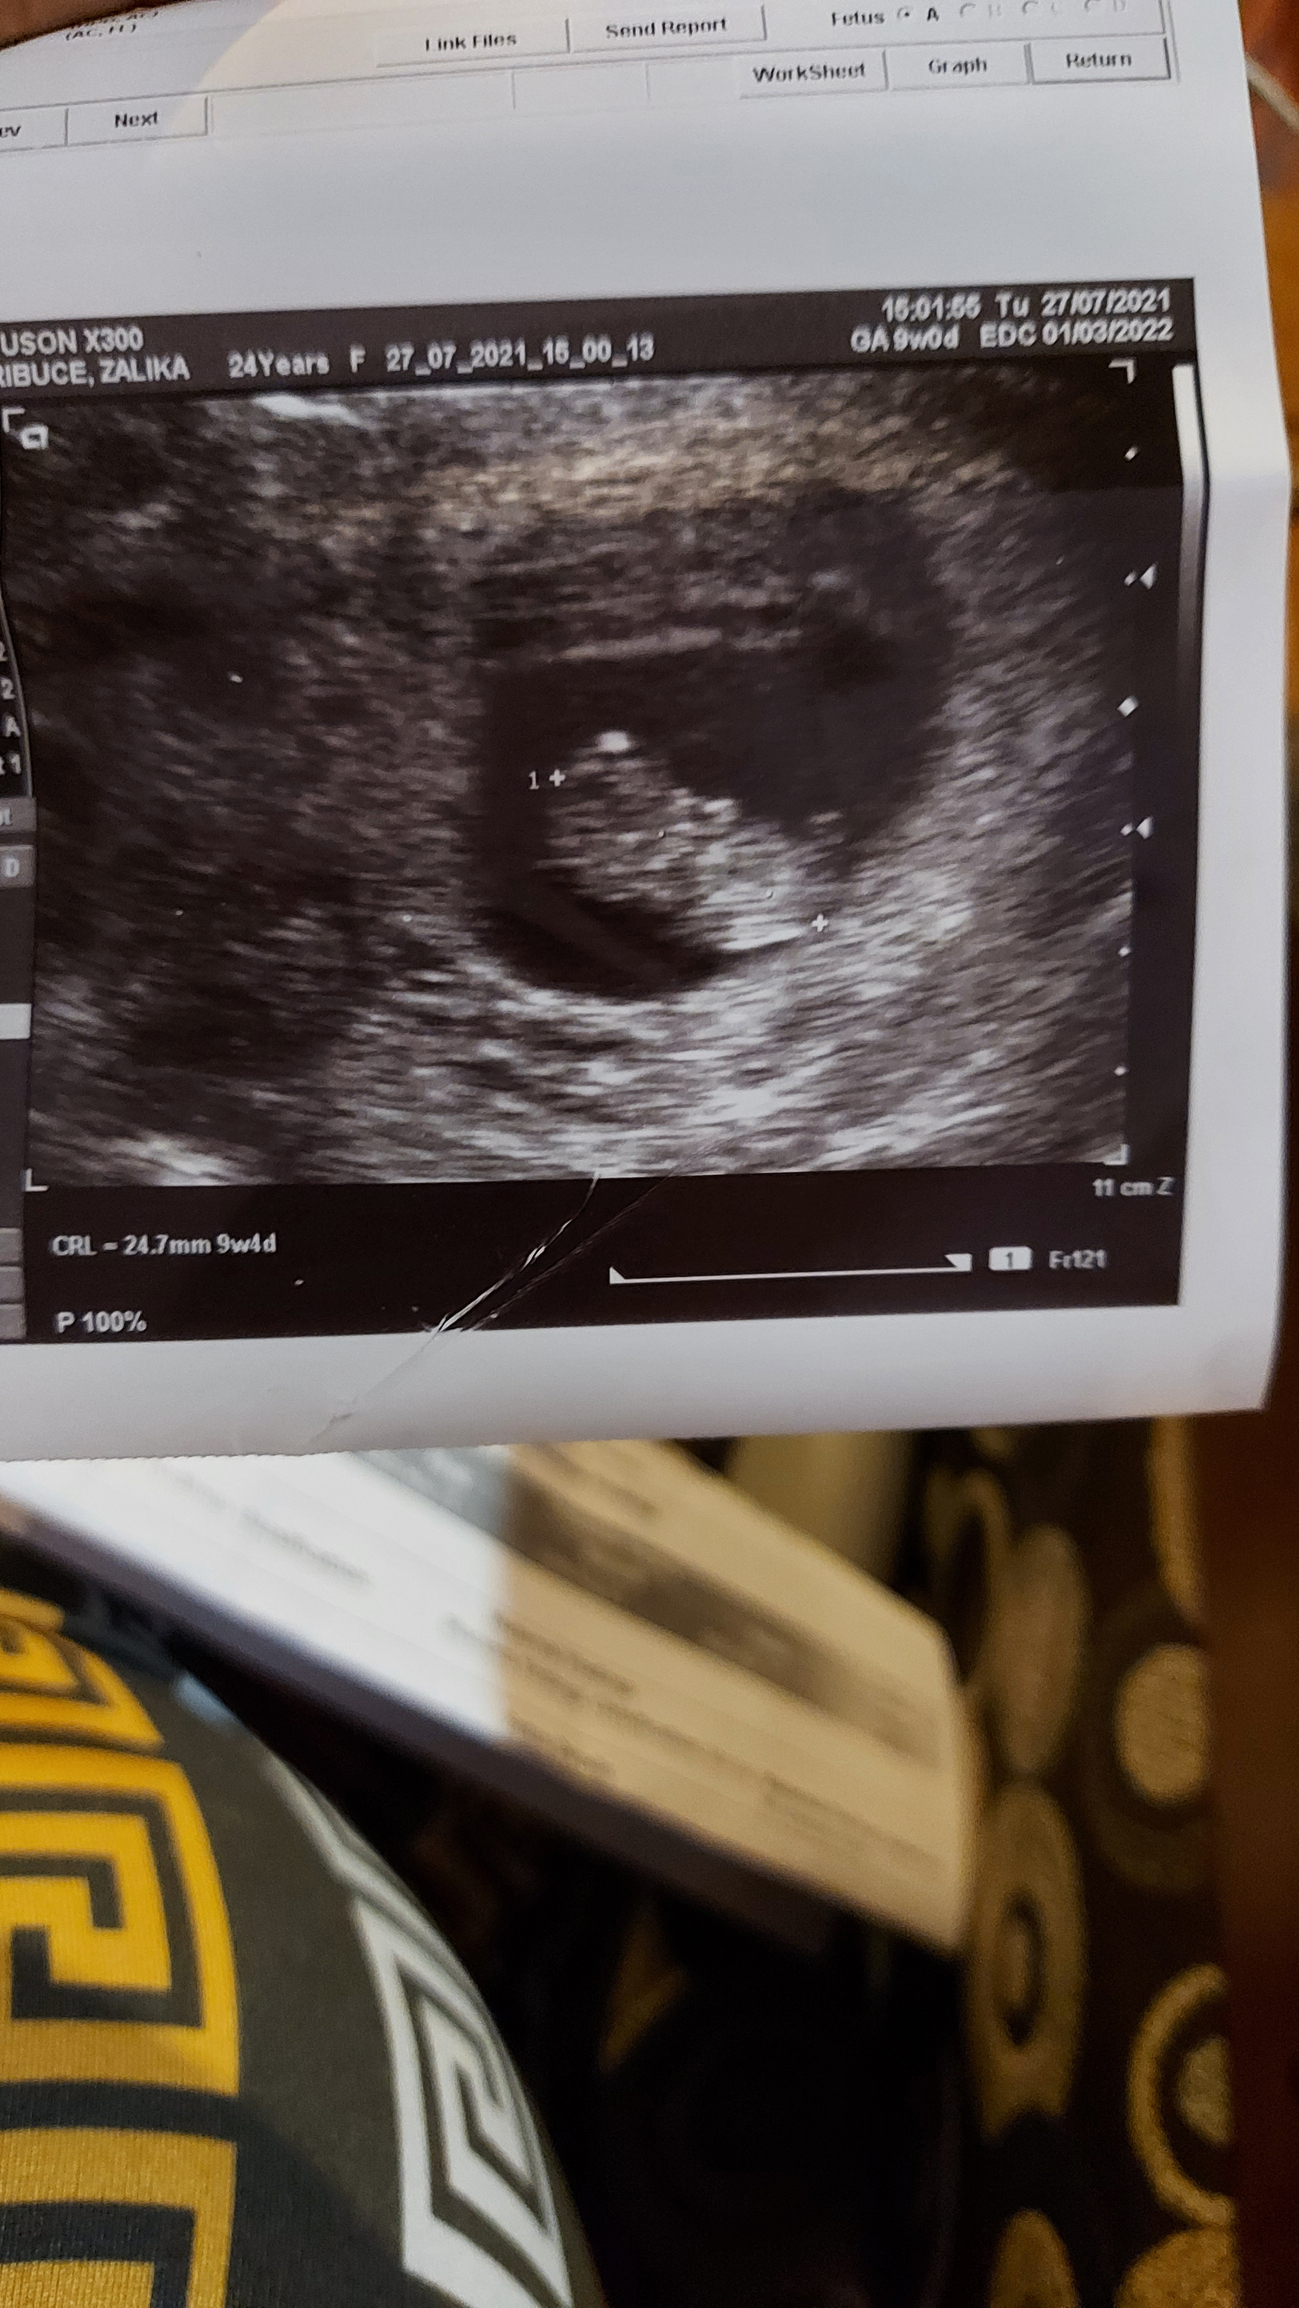

Hi hi anyone does the ramzi theory? 😊

Re: Hi hi anyone does the ramzi theory? 😊

• @lika_07 Congratulations! I don't know anything about the Ramzi theory, but we have a specific thread for all things ultrasound so you'll likely get more responses if you post this in there. You should also post an introduction on our intro thread, take a look at the board's rules and jump in to some of our other threads. This is a great board with a lot of great people so I hope you stick around and get to know everyone:)